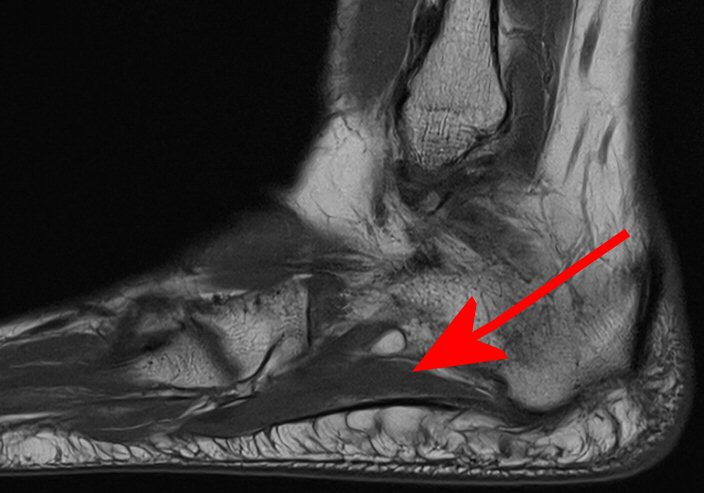

Kompression av n. planteris lateralis (gren av n. tibialis) mellan mm. abduktor hallucis longus och quadratus plantae [1, 2]. Nerven förmedlar sensorik från kalkaneus och motorik till mm. abduktor digiti minimi, flexor digitorum brevis och quadratus plantae [2].

Klinisk diagnos, vid behov MR som visar atrofi av m. abduktor digiti minimi.